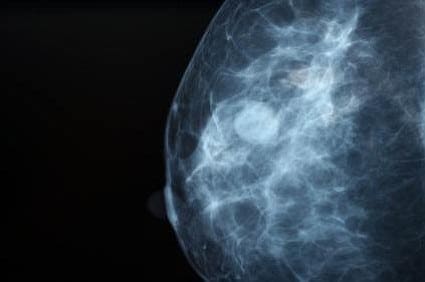

Fact: Regular mammograms are the best tests doctors have to find breast cancer early. The Centers for Disease Control and Prevention reports mammograms can detect cancerous tumors sometimes up to three years before they can be felt.

Fact: Mammograms aren’t perfect, but they are our best tool for early detection. When cancer is present, mammograms are about 80 percent effective in identifying it. Regular screenings help decrease the 20 percent of false negative results.